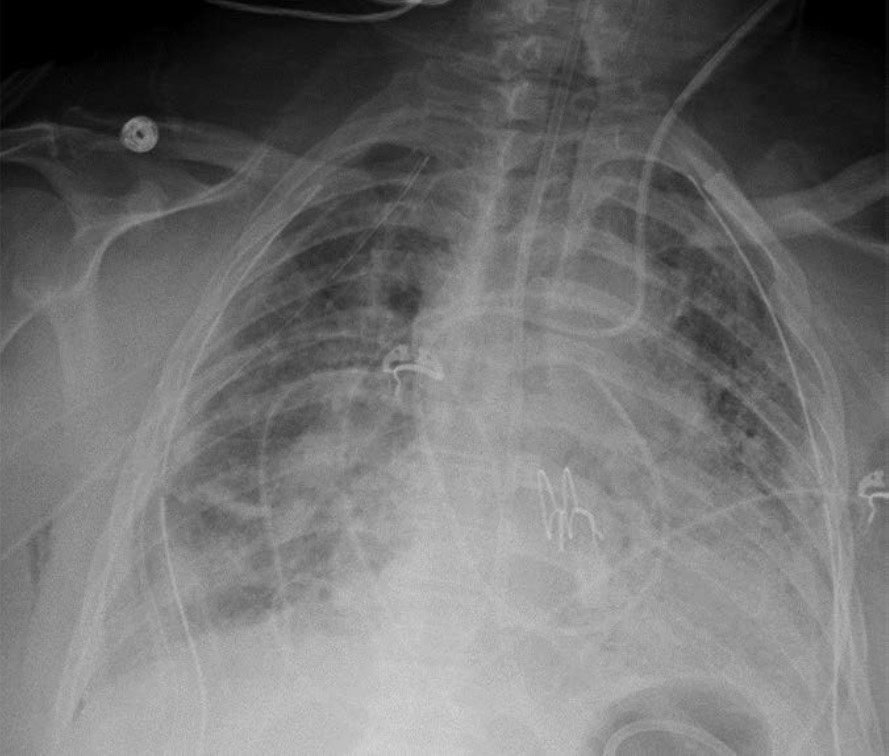

Primary graft dysfunction (PGD) is a transient complication that occurs within 24–72 hours after lung transplant and tends to resolve by postoperative day 5–10. PGD is thought to be secondary to ischemic injury of the allograft before and during transplant and secondary to reperfusion injury after transplant. PGD occurs in approximately 10–30% of lung transplant recipients [5]. On imaging, it manifests as perihilar and lower lung–predominant airspace and interstitial opacities and is similar in appearance to pulmonary edema. Clinically, PGD is graded from 0 to 3 on the basis of the presence or absence of imaging abnormalities and the severity of hypoxemia [6]. In patients who have undergone a unilateral lung transplant, PGD and pulmonary edema can be differentiated by observing the distribution; PGD affects only the lung allograft, whereas pulmonary edema affects both the lung

allograft and the native lung. Like acute rejection, PGD is considered a risk factor for chronic lung allograft dysfunction. It is treated with supportive care, such as mechanical ventilation and extracorporeal membrane oxygenation. Figure 3 shows a patient with PGD.